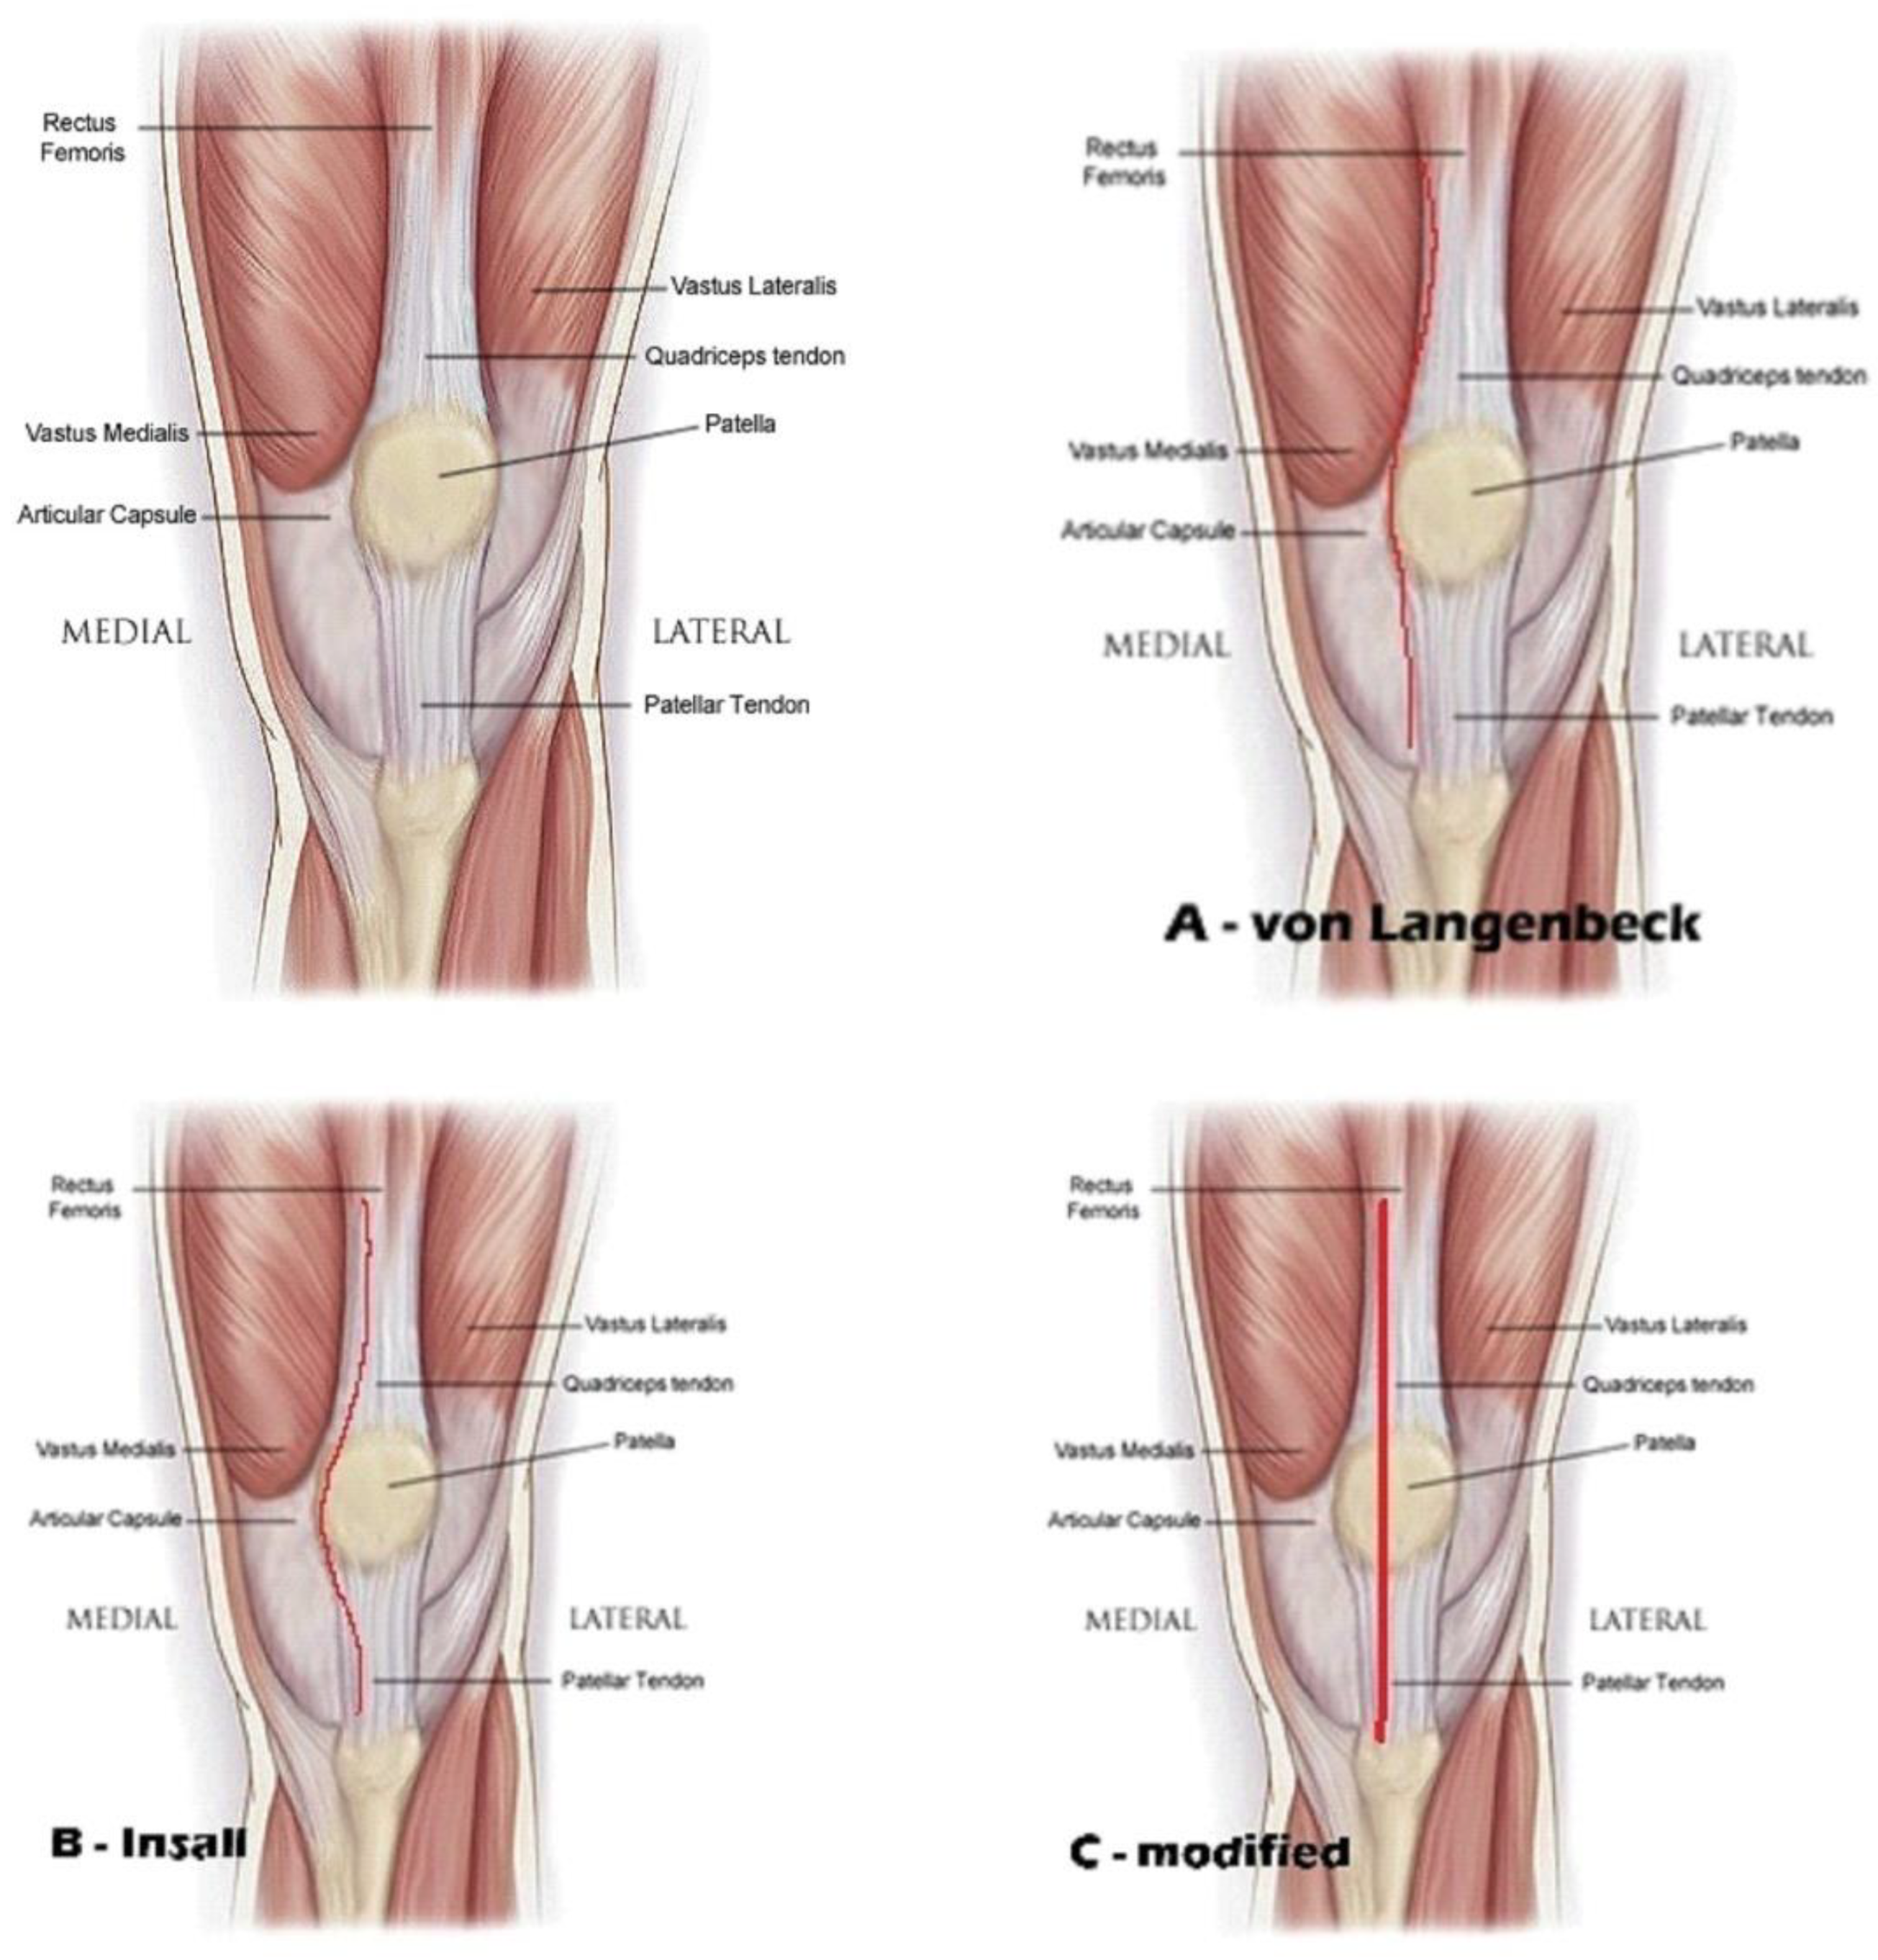

One of the most effective orthopaedic operations done today for individuals experiencing pain from a range of ailments is total knee arthroplasty (TKA). The knee joint is well exposed via the medial parapatellar approach. For complete knee replacement, the medial parapatellar approach has been the accepted method. Von Langenbeck described the medial parapatellar approach in 1878, however the optimal surgical method is still up for debate.

In order to reconstruct the medial joint capsule, von Langenbeck explained the procedure, which left a cuff of tissue on the patella and followed the medial boundary of the quadriceps tendon [1]. One critique of this strategy was that it upset the quadriceps mechanism at the point where the quadriceps tendon and vastus medialis meet, which led to the patella being unstable.

A variant of this technique was reported by Insall in 1971, which entailed severing the quadriceps tendon at the junction of the medial third and lateral two-thirds [2]. But the cuff that would be utilized for repair was blocked by the cut, which ran along the medial border of the patella.

We modified this medial approach, by making an incision at the internal border of the quadriceps tendon leaving 3-4 mm on internal side, peeling from patella almost half of fibrous - tendinous part and continue on the patella tendon leaving 3-4 mm on internal side. We repair the medial joint capsule and the continuity of the extensor mechanism by two or three bone tunnels on the patella to reinsert the tendinous peeling from the patella, we name this - transtendinous approach of the extensor mechanism in TKA. (Figure 1)

Figure 1. Medial parapatellar arthrotomy A - von Langebeck B – Insall C - modified.